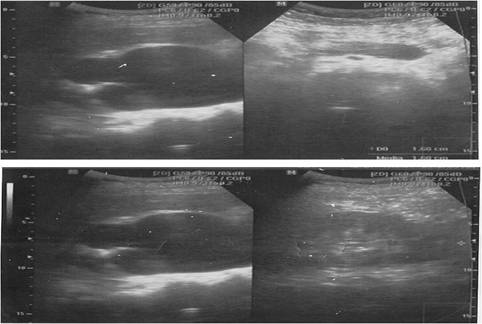

Ecografía renal (fig. 1): marcada ureterohidronefrosis derecha, con escaso parénquima de 8 mm. Ureteropielocaliectasia izquierda donde el tercio superior del uréter medía 13 mm y la pelvis renal 26 mm.